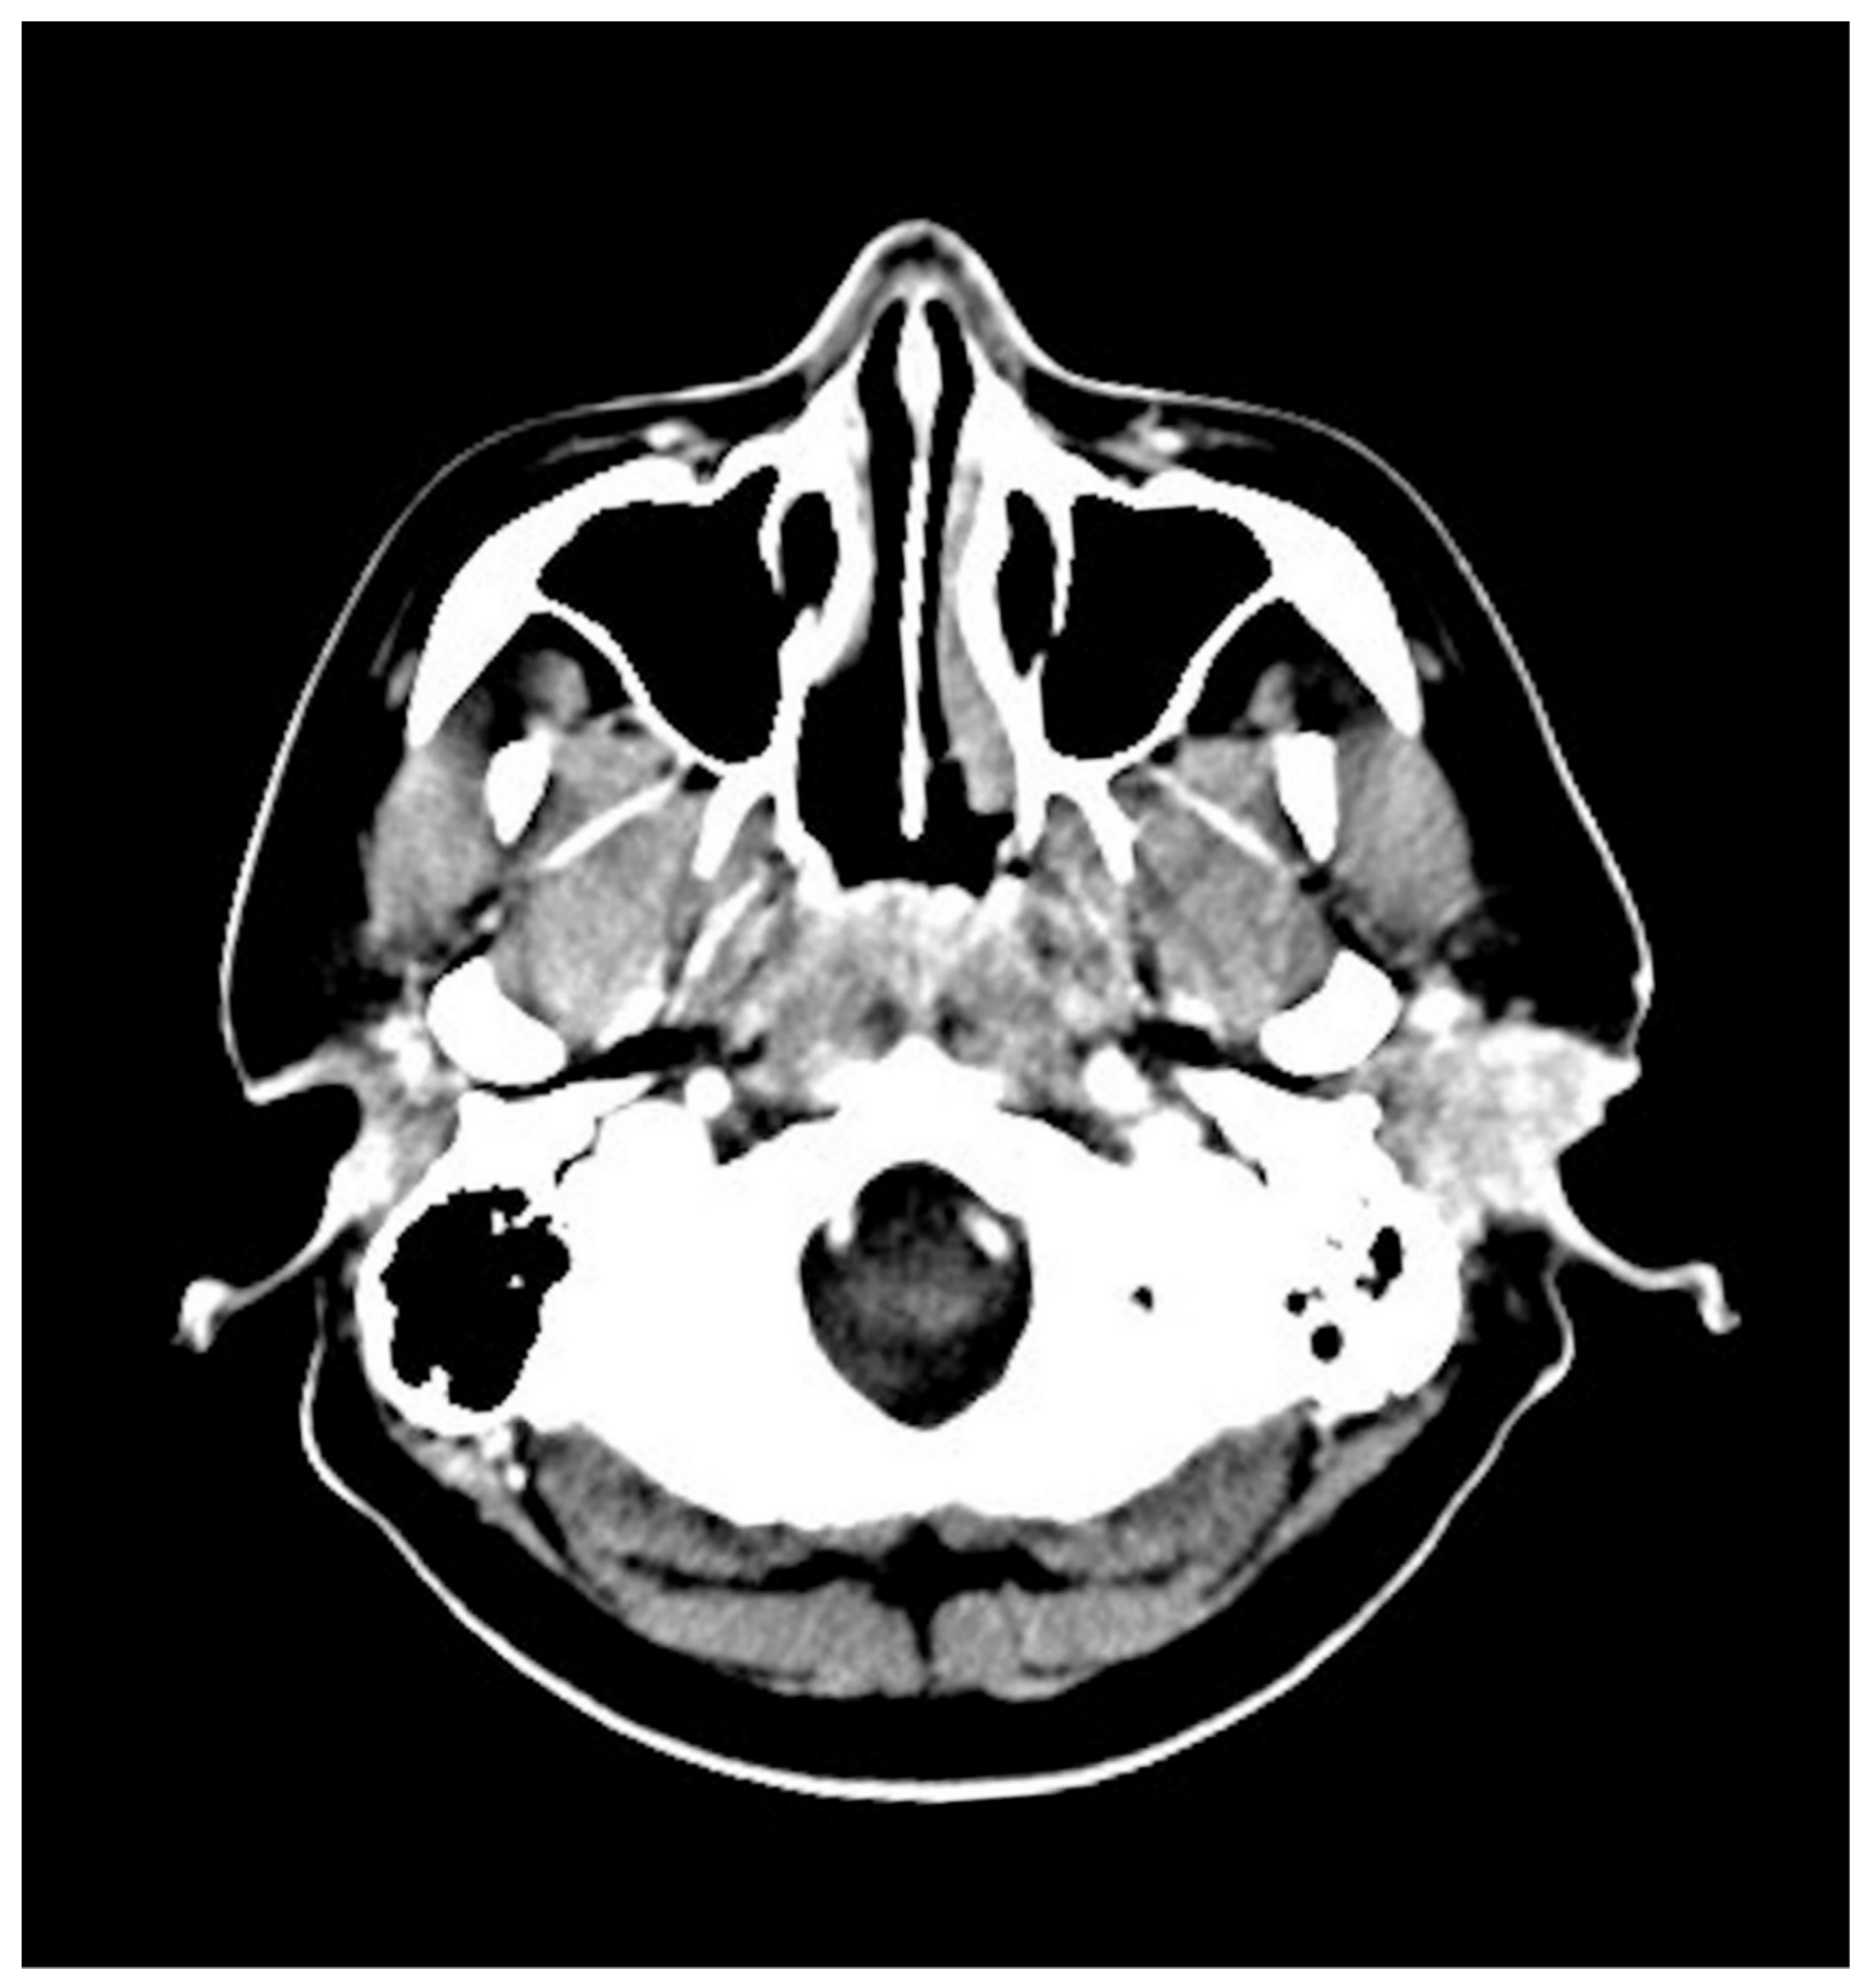

2. Case Presentation

| Present case, 2021 | Male | 34 | Painless mass | No osseous erosion | Radio-uptake | CD3, CD30 | Positive | CCRT |